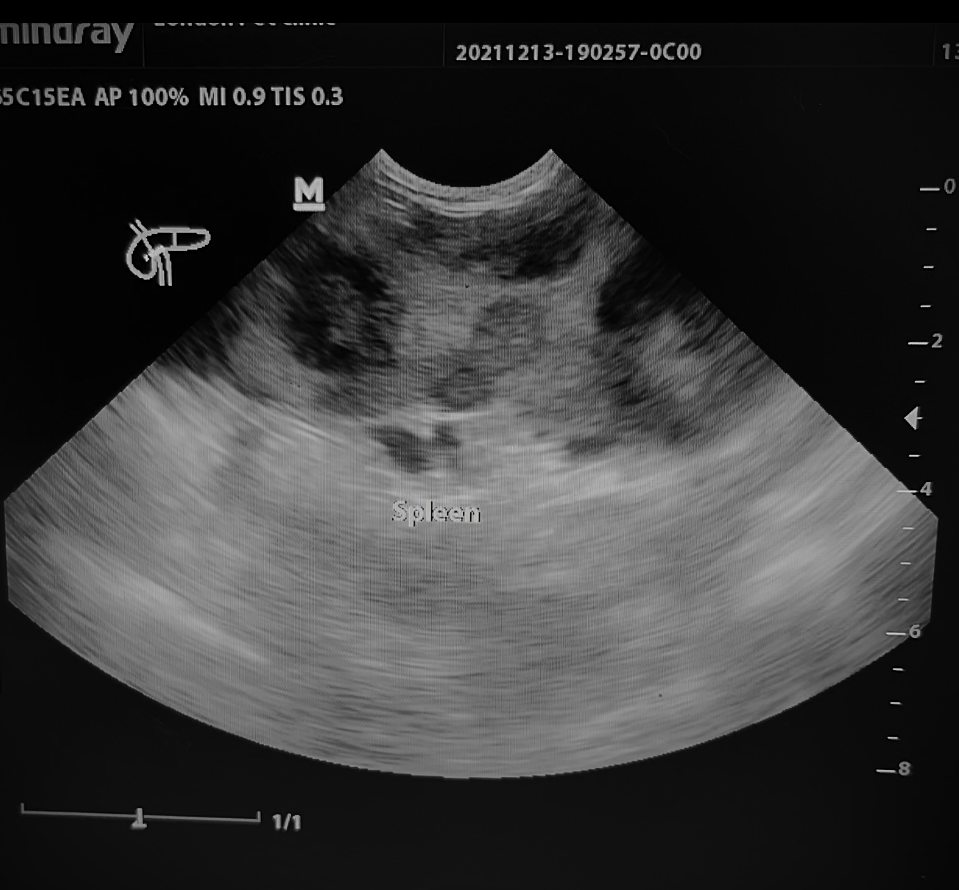

Abdominal Ultrasound:

• Large, irregular splenic masses (~18 cm )

• Free abdominal fluid

• No obvious liver metastases, but small hypoechoic nodules present